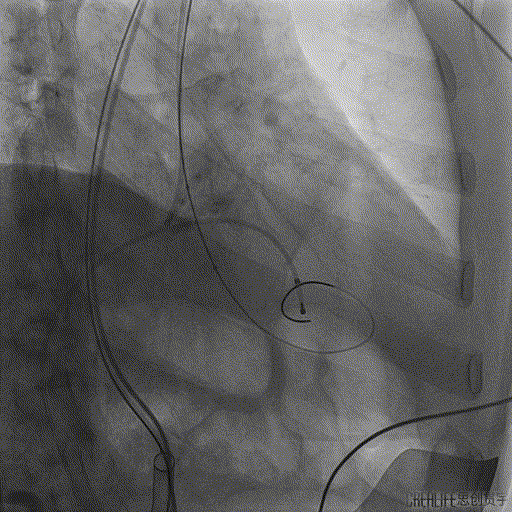

术中DSA影像